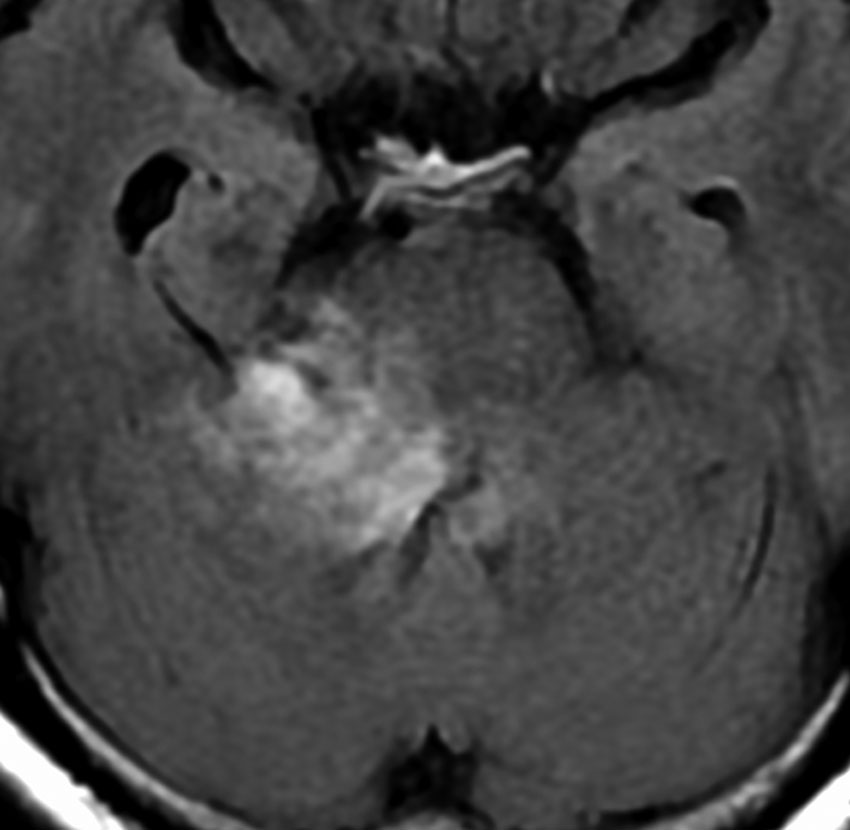

何も考えないで手術しなければならない時

聴神経腫瘍でまず手術が必要なのは巨大なものです。この4枚の写真は私が実際に手術をした患者さんのものです。脳幹部という脳の最も大切なところが腫瘍によって圧迫されて変形しているのが特徴です。右上のものはのう胞性腫瘍なので大きさの割に手術のリスクは高くありませんが,左上のものは実質性で出血性のものですごくリスクが高い手術でした。左下のものは普通のリスク。右下のものは超高難易度のものです。